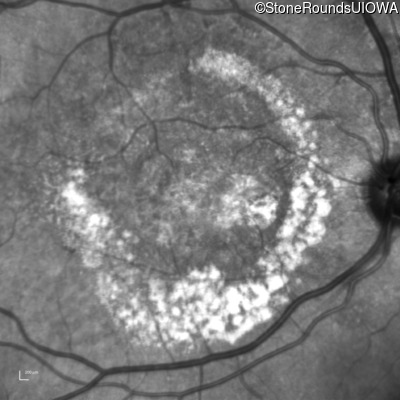

Age at visit: 59 years (Visit 3)

OD OS